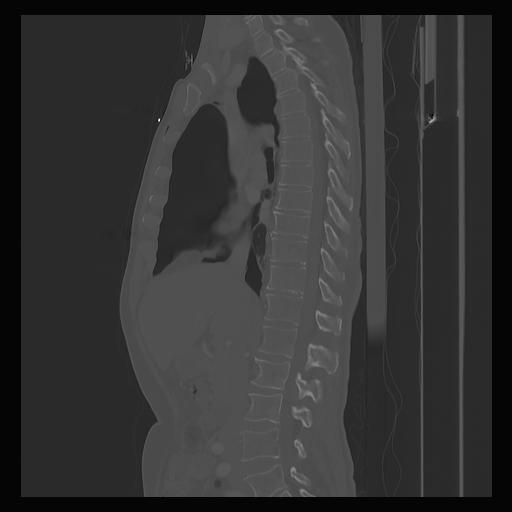

33 PULMON,CE,Sagittal,3.000,PULMON,Sagittal,